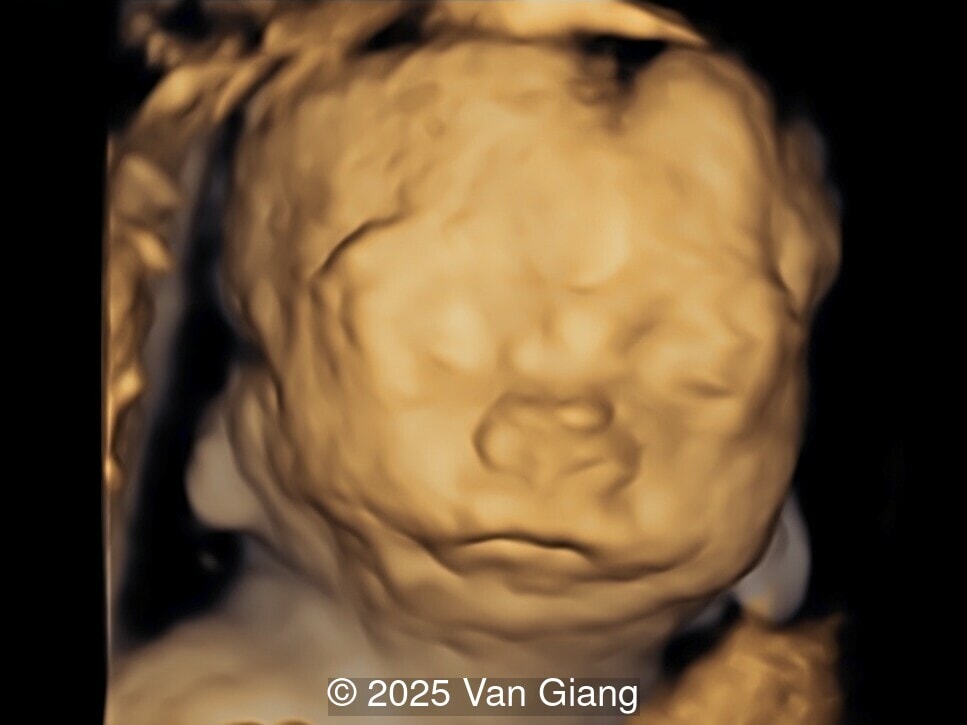

Image 2

Ultrasound revealed severe mandibular and zygomatic hypoplasia, glossoptosis, cleft palate, and micrognathia with an abnormal facial profile. Both upper limbs showed radial ray sequence with abnormal thumbs and shortened forearms. Unilateral clubfoot was also noted. No major cardiac or visceral anomalies were observed. Based on these findings, Nager syndrome was suspected.

fetal face

Image 2 fetal face